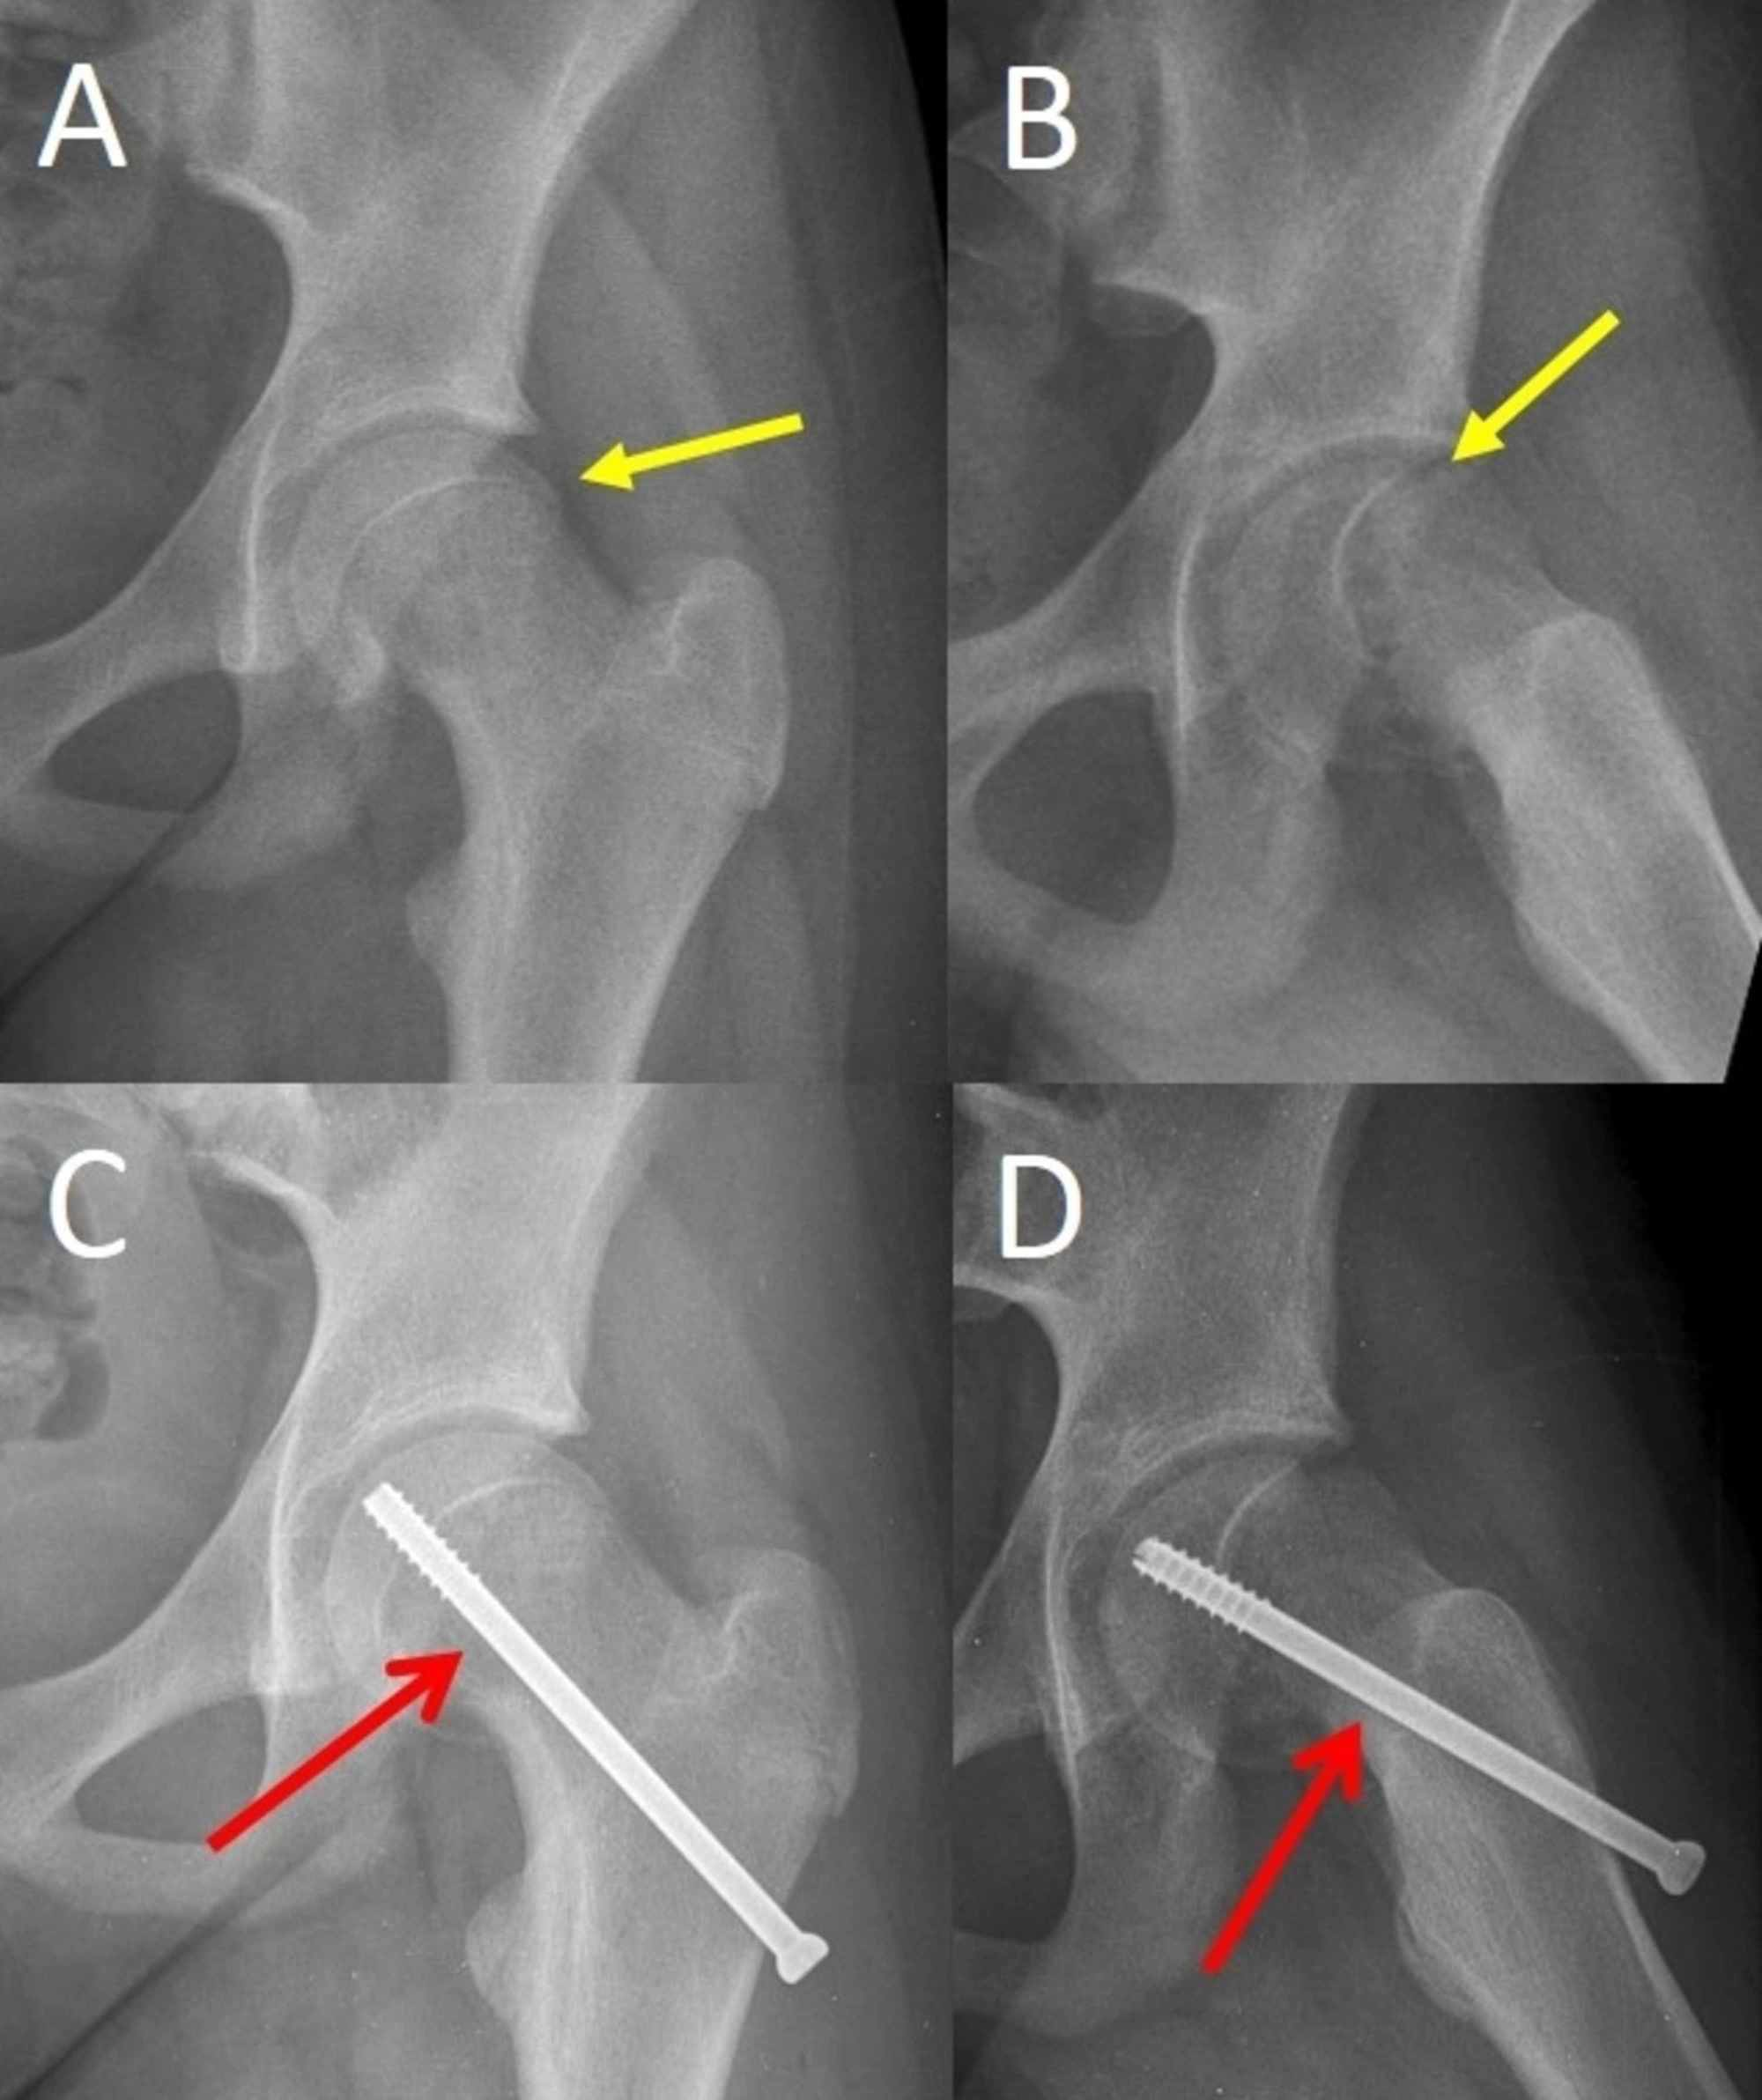

Femoroacetabular Impingement After Slipped Upper Femoral Epiphysis

boneandjoint.org.uk

boneandjoint.org.uk

The Frequency Of Sequelae Of Slipped Upper Femoral Epiphysis In Cam

boneandjoint.org.uk

boneandjoint.org.uk